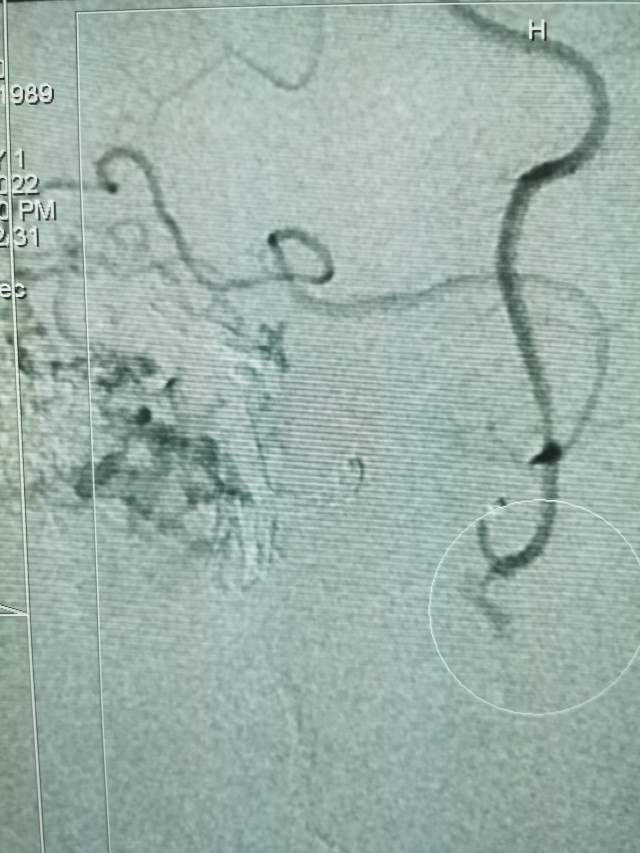

第一次手术:我们先超选6个分支小血管给予栓塞,去其枝叶,保留主干,结构逐步显山露水,清晰可见引流静脉的起始部,为二期手术做足准备~~~

第二次手术:继续采用削减周围边支的方法,术中显示3个瘤样凸起,如果提前闭塞引流静脉,这些薄弱结构会引起颅内出血哦,层层拨开畸形上面的面纱,最后安全的解决了畸形